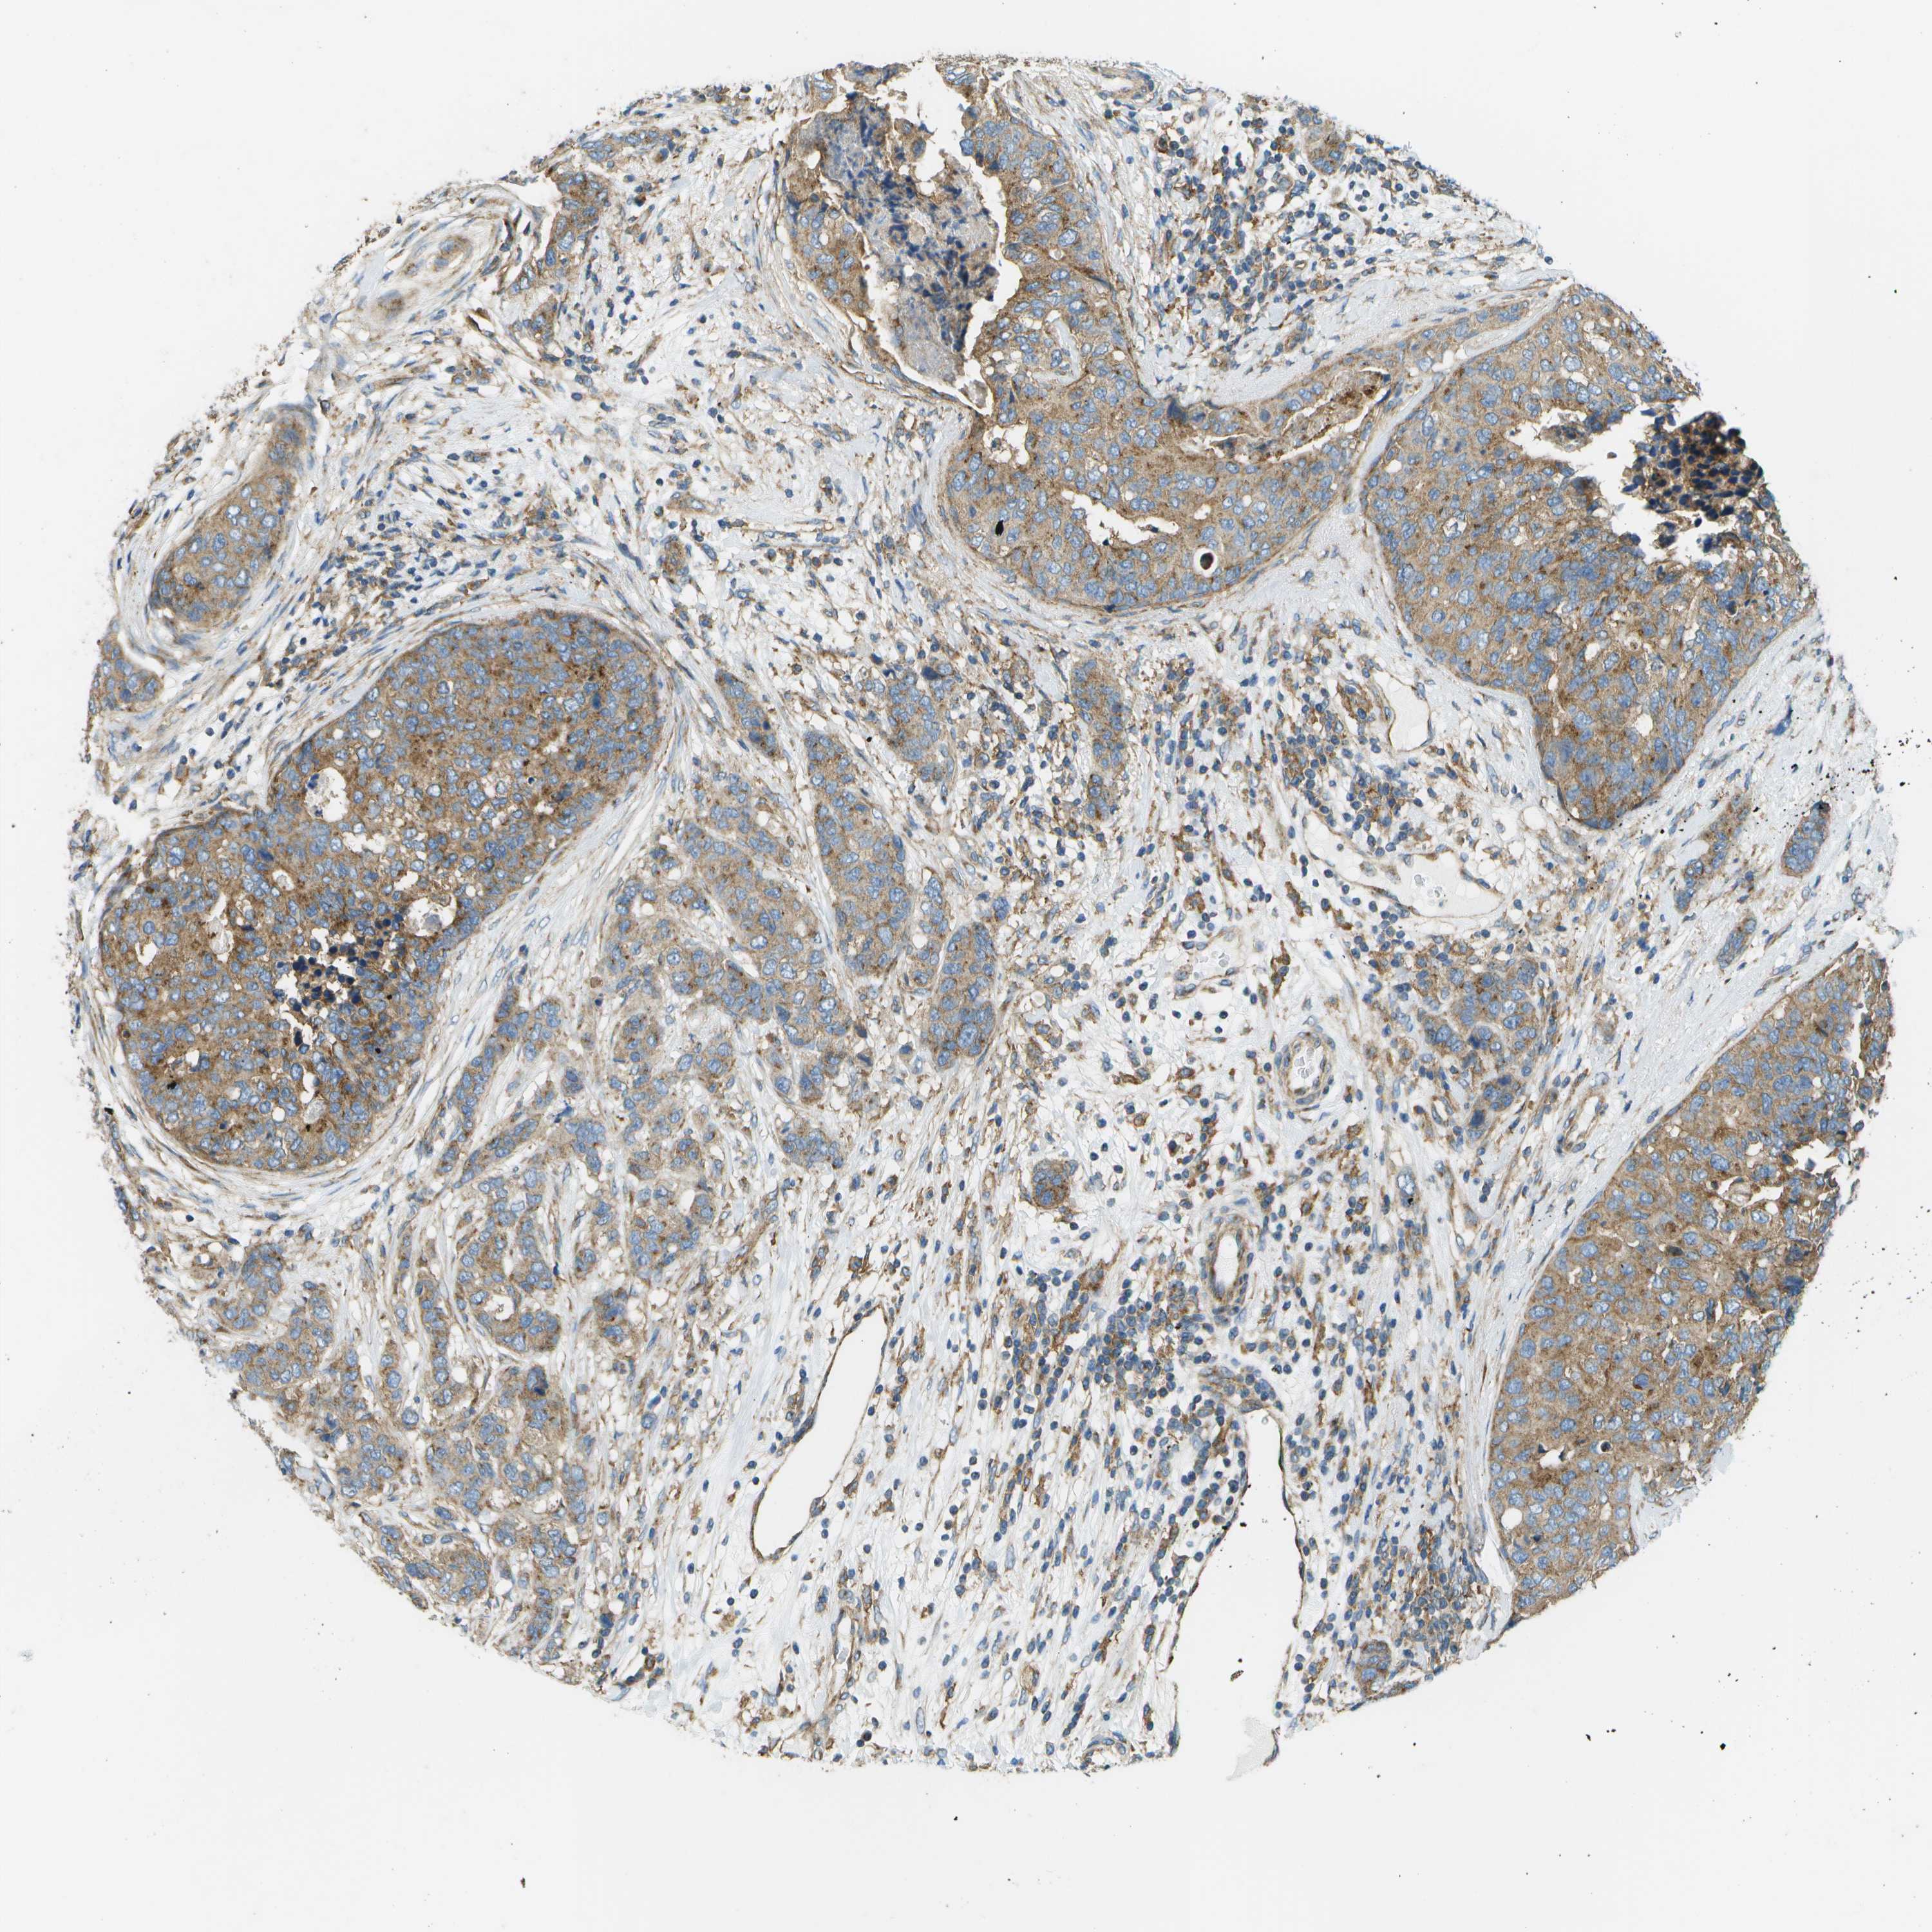

CANCER BREAST CANCER Show tissue menu

BRCA TCGA BRCA VALIDATION PROTEIN EXPRESSION